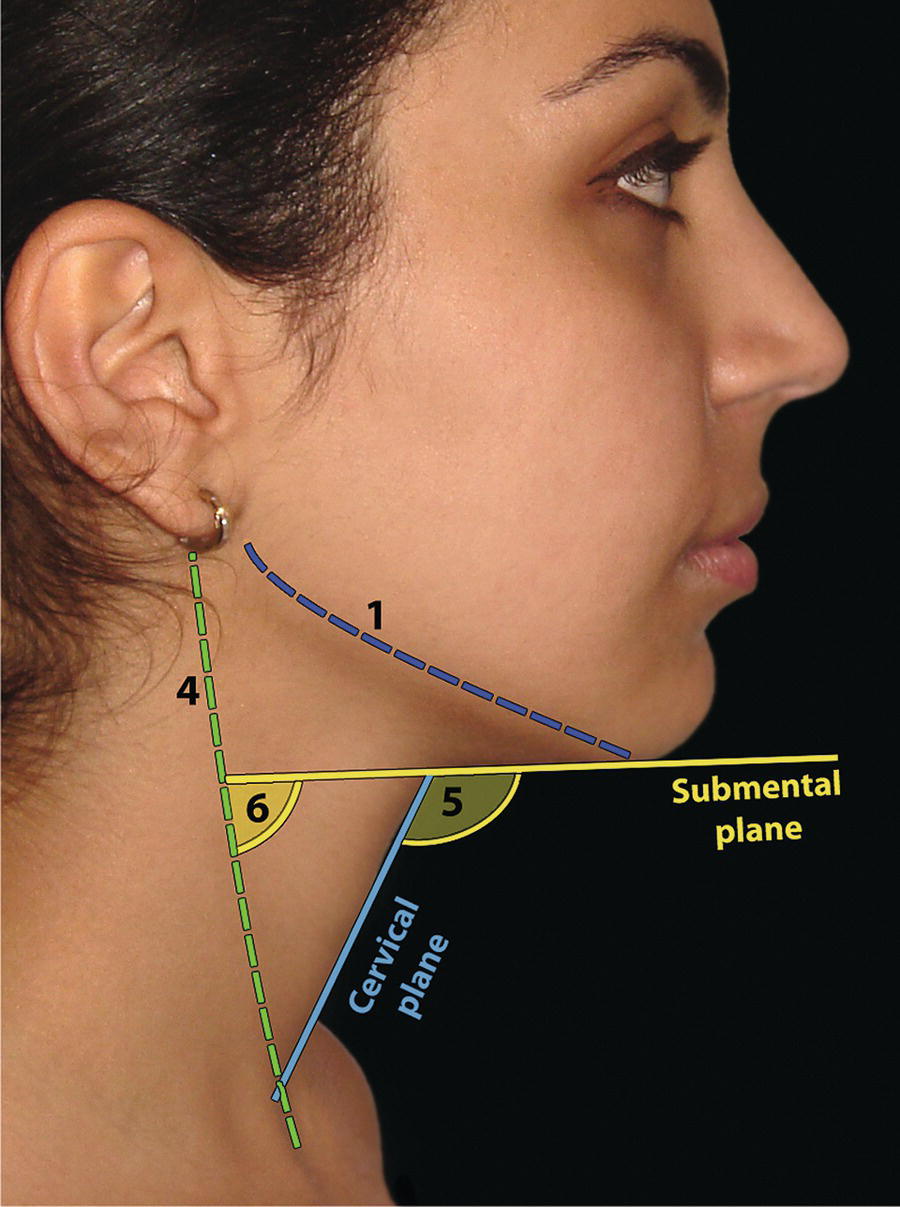

The morphology of the upper aspect of the neck and its transition with the submental region has a major impact on the aesthetics of the lower face. The anterior part of the neck extends no higher than the inferior border of the mandible. The hyoid bone is connected to the mandible by a thin sheet of muscle, the mylohyoids, which form the upper limit of the anterior part of the neck and separate the mouth from the neck. Superficially (i.e. below the mylohyoids) lies the anterior belly of digastric, while lying above it, half hidden under the mandible in the submandibular fossa, is the submandibular salivary gland (Figure 21.1). These structures are covered in by the investing layer of deep cervical fascia, which is attached to the hyoid bone and the inferior border of the mandible. The platysma muscle lies in the subcutaneous tissues. It forms a broad, flat sheet, extending from the deep fascia over the upper part of pectoralis major and the most anterior part of deltoid to the inferior border of the mandible, with some fibres reaching the lateral part of the lower lip. The sternocleidomastoid muscle forms a prominent neck landmark and may be made to stand out by turning the head towards the opposite side against resistance. The two heads of origin are from the sternum and medial one‐third of the clavicle; its attachment is to the mastoid process, which forms a readily visible and palpable bony landmark behind the lobe of the ear (Figure 21.2). Figure 21.1 Submental anatomy in relation to the mandible, with muscle attachments: Despite its importance in facial aesthetics, there is much confusion in terminology relating to the description and analysis of the submental‐cervical region. For example, the cervicomental angle has been described by perhaps half a dozen different methods, depending on the describing authority. Appropriate terminology is essential for the evaluation and accurate description of submental‐cervical aesthetics (Figure 21.3). Figure 21.2 Profile view of the face and neck with superimposed bony and muscular outlines: Cervical point (C‐point or ‘point C’): The innermost (posterior‐superior) point between the submental plane and the anterior aspect of the neck in the midsagittal plane, located at the intersection of lines drawn tangent to the submental region and the anterior neck. Submental plane: A plane or line constructed between the cervical point (C‐point) and the most inferior point on the chin (soft tissue menton, Me’). If C‐point cannot be defined, the submental plane is drawn tangent to the submental contour passing through soft tissue menton. The submental plane is referred to as the ‘throat’ plane by some authorities; the submental length (distance from C‐point to menton) is therefore sometimes referred to as the ‘throat length’. Cervical plane: A plane or line drawn tangent to the anterior soft tissue contour of the neck above and below the thyroid prominence. Figure 21.3 Submental plane, cervical plane and cervical point (C‐point). A thorough understanding of the aetiological factors involved in creating a poor aesthetic contour of the submental‐cervical region is required in order to diagnose and appropriately plan the correction of the aesthetic submental‐cervical angles and contour. The tonicity of the submental‐cervical skin, the muscular support of the neck, the isolated fatty deposits in the submental‐cervical region, the skeletal framework of the mandible and chin, and the spatial position of the hyoid bone are all important parameters in the aesthetic analysis of the submental‐cervical region. An undesirable submental‐cervical contour may result from: It is paramount that the clinical evaluation is undertaken with the patient in natural head position (NHP). Even a small degree of upward or downward tilting of the head must be avoided as it may have a profound effect on the contour of the submental‐cervical region. A number of parameters may be analysed in the clinical evaluation of the submental‐cervical region: Mandibular and/or chin deficiency in the sagittal plane, and/or posterior (downward and backward) rotation of the mandible, often secondary to vertical maxillary excess, may contribute to the undesirable aesthetic appearance of the submental‐cervical region (Figure 21.4). It is helpful to have the ‘Class II skeletal pattern’ patient posture the mandible forward to a more normal sagittal position, which will concurrently stretch the submental soft tissues. If this manoeuvre improves the submental‐cervical aesthetics visually, and tightens the submental soft tissues to palpation, then correction of the underlying skeletal discrepancy is likely to improve the submental‐cervical aesthetics (Figure 21.5). Figure 21.4 Class II jaw relationship due to mandibular deficiency and significant compensatory proclination of the mandibular incisor teeth; the submental‐cervical angle is increased. Figure 21.5 (A) Patient with Class II jaw relationship due to mandibular deficiency. (B) Posturing the mandible forward to a more normal sagittal position will concurrently stretch the submental soft tissues. Figure 21.6 Skin laxity test. The converse is also true. Surgical procedures to set back the mandible, or set down the maxilla causing posterior mandibular rotation, will tend to have undesirable consequences on submental‐cervical aesthetics (see Figure 19.22). The patient must be informed of these potential untoward consequences of orthognathic surgery, and should be advised of the possible future need for aesthetic surgical procedures of the submental‐cervical region. The laxity of the submental‐cervical skin may be evaluated by the skin laxity test: the clinician stands behind the patient and gently pulls the soft tissues upward and backward just inferior and anterior to the ear, simulating a neck lift (Figure 21.6). If the soft tissues are easily displaced upward there is increased laxity of the skin, termed redundant skin.1 If following this manoeuvre there is still submental fullness, the patient has redundant skin and excessive submental‐cervical adiposity. Reduced tonicity of the platysma may contribute significantly to submental fullness.2,3 In addition, the platysma muscle may or may not merge anatomically across the midline. Frequently, excessive submental fullness results not only from redundant skin but from the redundant medial borders of the platysma muscle that fail to meet in the midline. Increased submental‐cervical fat accumulation may be independent of generalized body fat; in some patients subcutaneous fat accumulation in this region may remain despite extensive weight loss. In younger patients the fat usually accumulates between the skin and the platysma muscle. In older patients, the fat may accumulate both deep and superficial to the platysma (Figure 21.9). The quantity of submental fat may be estimated by the submental pinch test: the submental soft tissues are gently gripped between the thumb and index finger.1 This manoeuvre should be performed with the patient both in NHP and with the head extended and contracting the platysma muscle; in this way the clinician may determine whether the submental fat is predominantly supraplatysmal or subplatysmal. Figure 21.7 Platysma view: With the head tilted slightly back in frontal view, grimacing and clenching the teeth will induce contraction of the platysma muscle. The muscular fascicles of the platysma become visible beneath the skin. Figure 21.8 Platysmal bands may be evident in repose in an ageing neck. Figure 21.9 Submental adiposity. Figure 21.10 The definition of the inferior border of the mandible is an important aesthetic parameter as it defines the demarcation between the face and neck. (Detail, Woman’s Head, Leonardo da Vinci, c. 1470–76, Galleria degli Uffizi, Florence.) The definition of the inferior border of the mandible, from the chin to the gonial angle, is an important aesthetic parameter, as it defines the demarcation between the face and neck (Figure 21.10). In frontal view, the transition from the upper aspect of the neck to the inferior border of the mandible has a subtle hourglass appearance, with its superior aspect being well defined by the concavity immediately below the inferior mandibular borders (Figure 21.11).1 The soft tissues of the neck normally closely adhere to the structures underlying them. Lack of definition of the inferior mandibular border may be due to increased soft tissue laxity, fat accumulation, mandibular/chin deficiency or hyoid bone sag. Figure 21.11 In frontal view, the transition from the upper aspect of the neck to the inferior border of the mandible has a subtle hourglass appearance. The submandibular salivary gland envelopes the posterior border of the mylohyoid muscle, half hidden in the submandibular fossa on the medial aspect of the mandible (see Figure 21.1). Submandibular fullness may result from an increase in size of the submandibular gland, laxity of the neck fascial layer or submandibular gland ptosis. Rhytidectomy and platysma plication address this problem indirectly by increasing the fascial support for the gland. However, patients may develop a more noticeable submandibular fullness as the removal of submental fat unmasks the ptotic gland. Partial or complete submandibular gland resection provides definite improvement of submandibular fullness resulting from glandular hypertrophy or ptosis, but may be considered too radical for a patient with a normal‐sized, ptotic submandibular gland. Guyuron et al.4 have described the basket submandibular gland suspension technique, directly supporting the gland onto the inner aspect of the inferior surface of the mandible with a strong piece of fascia. This technique helps eliminate submandibular fullness in patients with normal‐sized, ptotic glands. Resection remains the treatment of choice for the correction of glandular hypertrophy. Figure 21.12 Of the ‘six visual criteria’ of the profile view for ‘success in restoring the youthful neck’, the following are demonstrated: 1 Distinct inferior mandibular border 4 Visible anterior border of sternocleidomastoid muscle 5 Submental‐cervical (submental‐neck) angle between 105° and 120° 6 Sternocleidomastoid‐submental plane (SM‐SM) angle approximately 90°